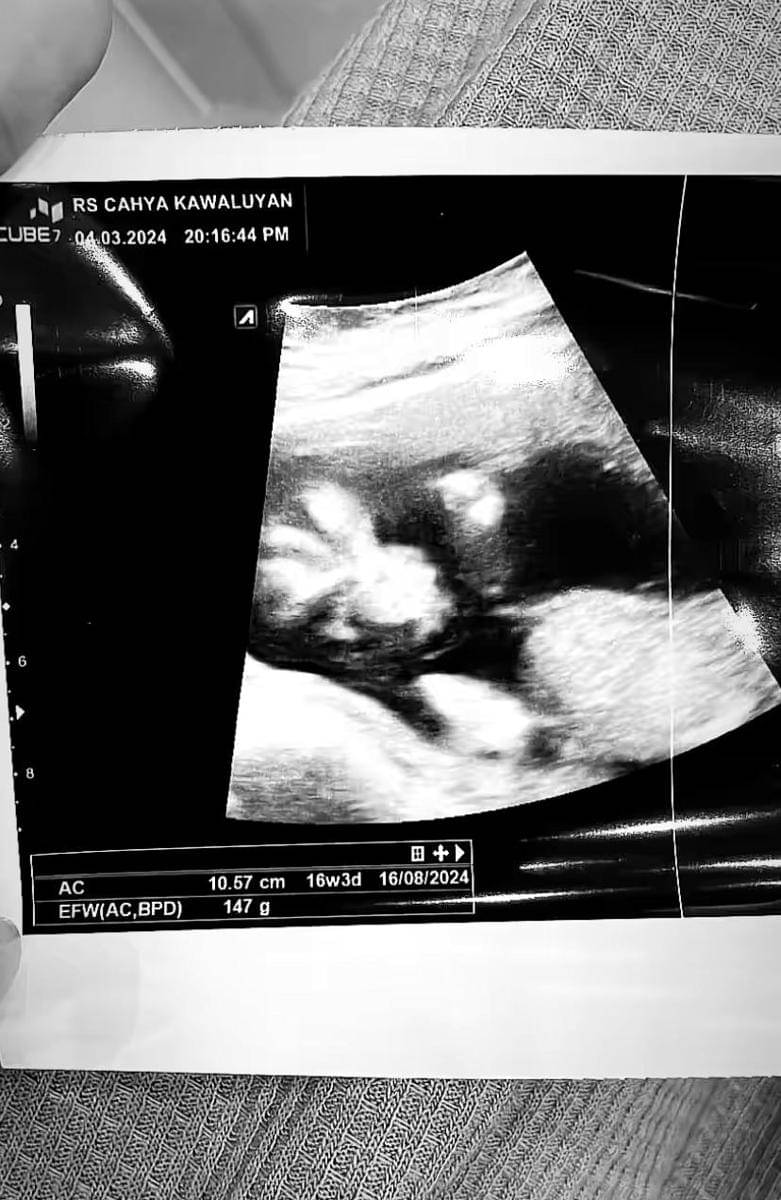

2. Kabar bahagia ini diungkap oleh Iqbal Rosadi lewat potret USG yang diunggah ke Instagram-nya, Jumat (8/3/2024)

3. Melansir keterangan dalam potret di USG, terungkap kandungan Nadya sudah berusia 16 minggu lebih 3 hari

4. Dalam caption-nya, Iqbal menuliskan pesan singkat, tapi menyentuh. "Doa terbaik untuk kita semua," tulisnya